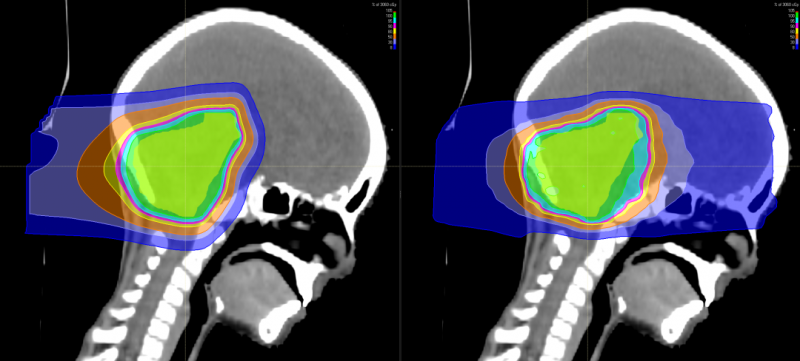

上图为髓母细胞瘤对全脑全脊髓照射剂量的分布图比较,传统放疗会对身体造成大范围的损害,波及脊柱周边的脏器,而质子治疗剂量分布图,脊髓周边的照射剂量机乎为零,不会造成损害及副作用。